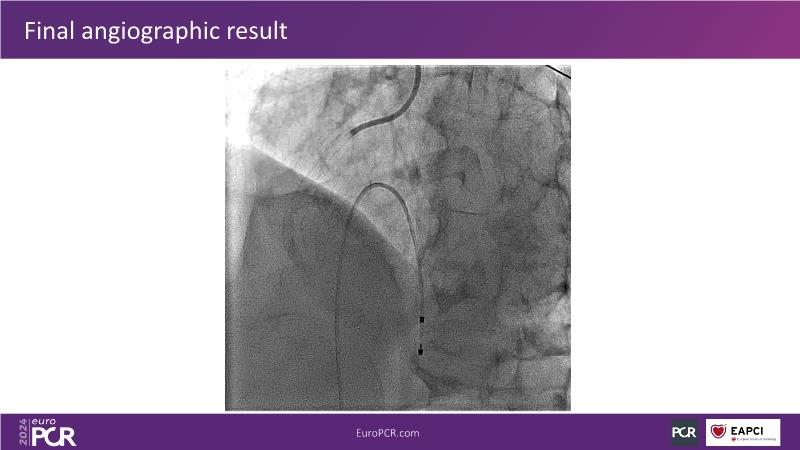

Tune into this 2024 session for insights into the latest ESC guidelines, strategies to prevent and treat no reflow, and an examination of trials like TASTE, TAPAS, and TOTAL on coronary thrombus management. Explore also the outcomes of the CHEETAH study, pondering a potential paradigm shift, and delve into a case study on thrombus removal in a patient with high thrombus burden.